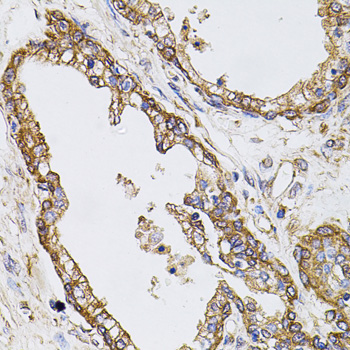

图片:

Immunohistochemistry of paraffin-embedded human prostate using CAST at dilution of 1:100 (40x lens).